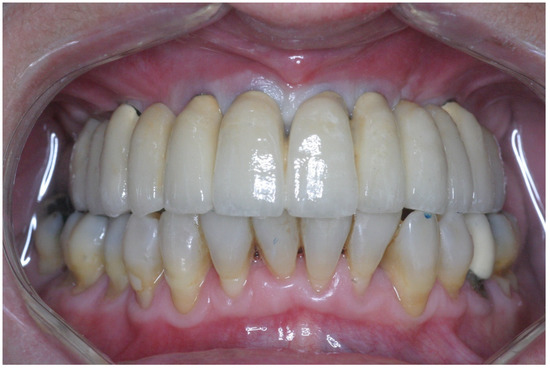

2.3. Prosthetic Protocol